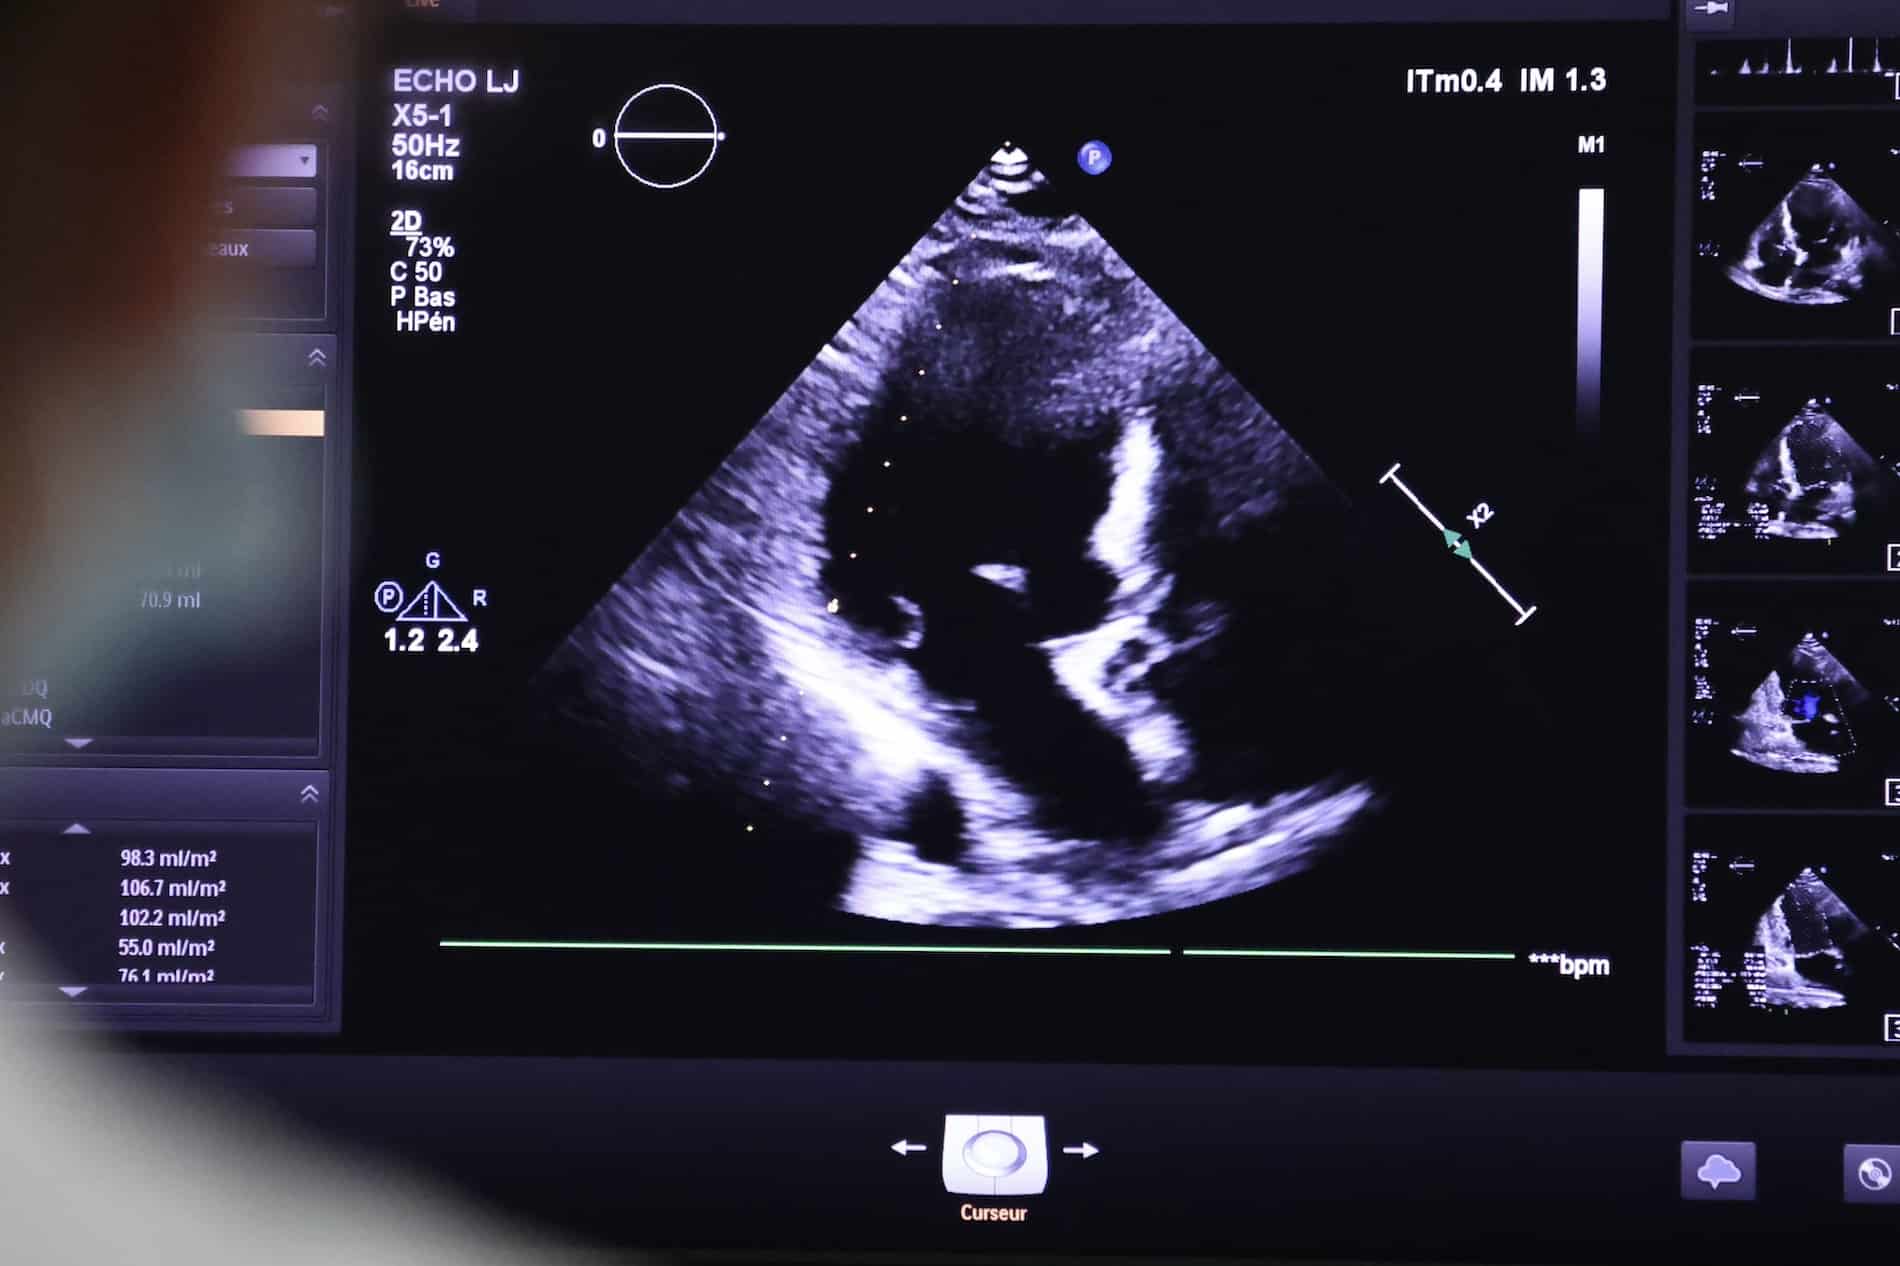

Echocardiographie transthoracique

L’échocardiographie transthoracique est un examen utilisé pour générer des images du cœur (cavités cardiaques et valves) et des gros vaisseaux (aorte, artère pulmonaire et veines caves). Des séquences sont réalisées sur plusieurs axes ou coupes et analysées en temps réel par le cardiologue ou le technicien spécialisé qui effectue l’examen. C’est exactement le même principe qu’une échographie dans le cadre d’un suivi de grossesse, mais au niveau du thorax.

Cet examen peut être utile en cas de suspicion d’une maladie cardiaque (par exemple si l’on présente des douleurs thoraciques à l’effort, un souffle au cœur, des palpitations). Il sert également à évaluer l’efficacité d’un traitement ou pour suivre l’évolution d’une maladie. L’échocardiographie transthoracique est indolore, non invasive et dure en général de 15 à 30 minutes.

Écho-cardiographie transthoracique